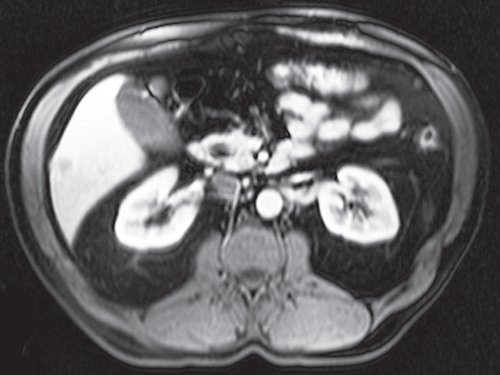

По данным МРТ (с контрастным веществом омнискан), в обеих долях печени выявлены единичные метастазы колоректального рака, размерами до 3,0 см (рис. 3-8).

Рис. 3. МРТ метастаза в печени с контрастным веществом омнискан, венозная фаза.

Рис. 4. МРТ метастаза в печени, корональная проекция.

Рис. 5. МРТ метастаза в печени, T2FS.

Рис. 6. МРТ метастаза в печени, Т2ВИ с жироподавлением.

Рис. 7. МРТ метастаза в печени, артериальная фаза.

Рис. 8. МРТ метастаза в печени, Т1ВИ.